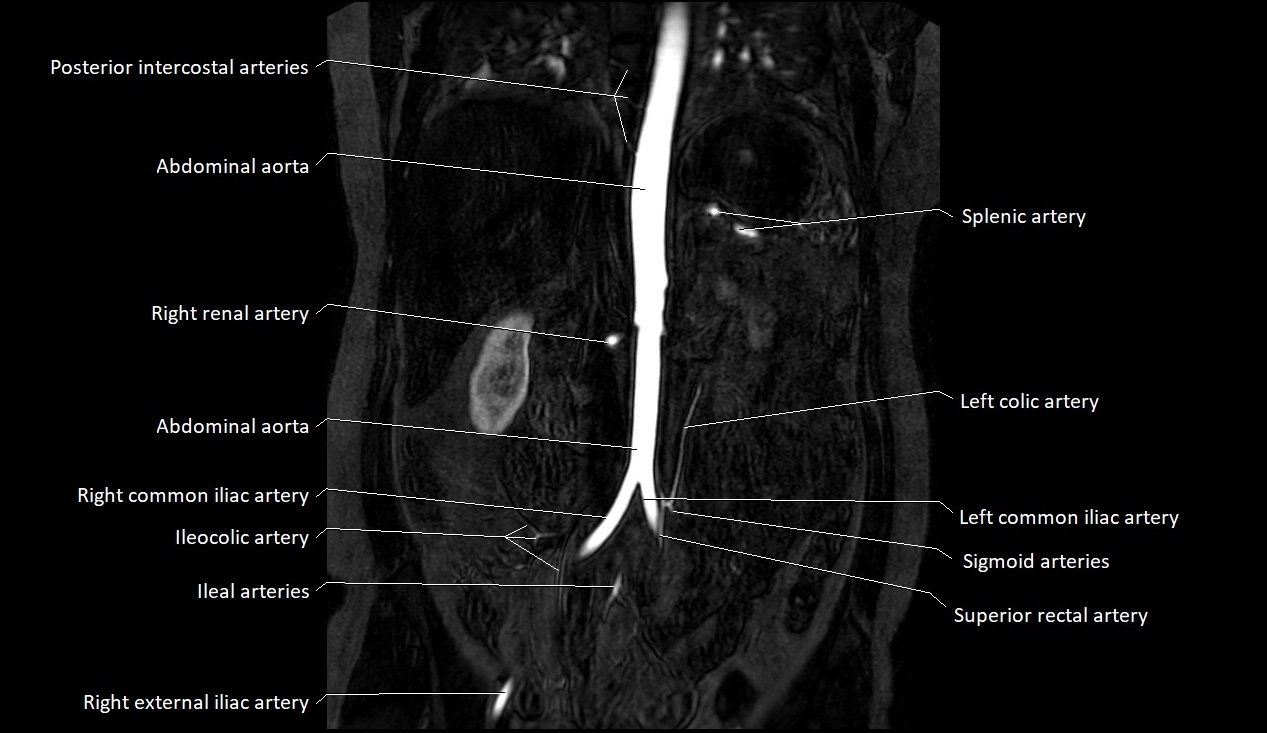

MRA (Magnetic Resonance Angiography):

• Contrast-enhanced MRA provides high-resolution imaging of the aorta and its branches

• Allows 3D reconstruction of visceral, parietal, and terminal branches

• Excellent for evaluating aneurysm size, dissection flap, stenosis, or preoperative planning

• Non-invasive alternative to conventional angiography

MRI images

image